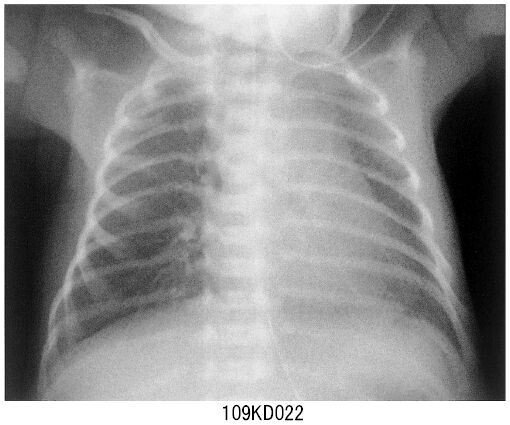

- 呼吸困難の原因について肺を研究するための胸部X線写真